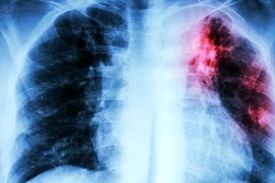

خبرمهم: سازمان جهانی بهداشت (WHO) در یک گزارش جدید اعلام کرد که برای اولین بار در ۱۵ سال گذشته، مرگ و میر جهانی سل در…